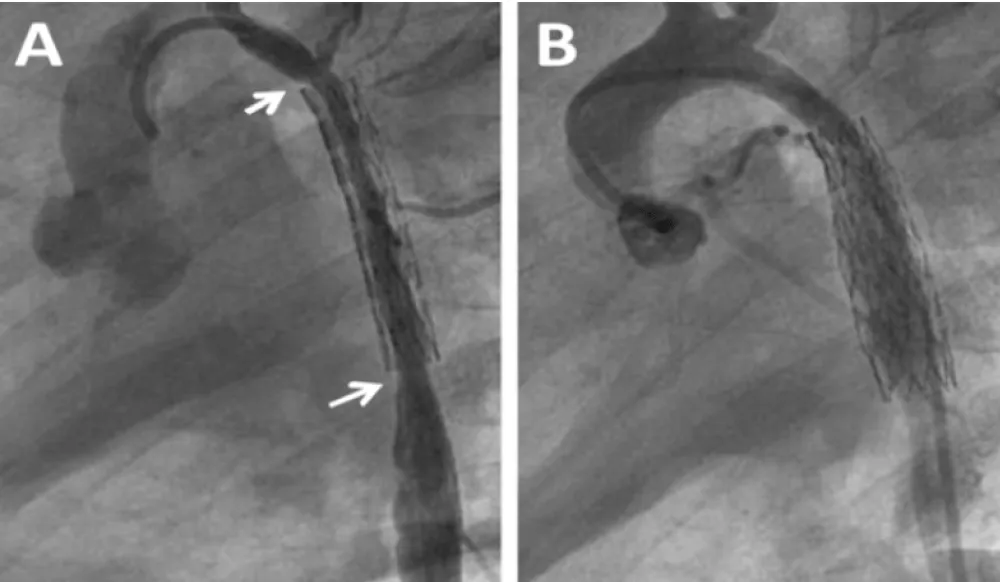

Enalapril was continued and dual anti aggregation was started with clopidogrel and aspirin. On follow-up the femoral pulses were weaker than the right brachial. Blood pressures could not be measured for persistent excessive irritability. At the time of multislice CT under general anesthesia, noninvasive blood pressure showed normal values for the right arm and moderate increase in the coarctation gradient (Table 1). CT imaging findings were no different to those following BA. The descending aorta distal to the stent remained narrowed reassuming a normal caliper at the diaphragm level. Two more BAs for recurrent coarctation were performed at age 3y 5m and 5m later. The former with right axillary artery access for recoarctation distal to the left subclavian artery which had severe ostial stenosis and subclavian steal (Figure 4A). The intrastent intimal proliferation was much less prominent than in the previous procedure and the coarctation diameter almost doubled (Figure 4B). The other intervention from the right femoral artery addressed the sub-clavian stenosis with disappearance of subclavian steal. The patient continues with antihypertensive and dual antiaggregation therapy. An extended patch angioplasty is expected in the future (Figure 4 A,B).

Figure 4: Balloon Angioplasty for Recurrent Coarctation at age 41 months. A: Recurrent coarctation proximal to the stent (left arrow). Severe stenosis at the origin of the left sub-clavian artery (right arrow). Intrastent proliferation much less evident than in previous procedure; B: Successful dilatation of the coarctation with right axillary approach. The sub-clavian stenosis was addressed with femoral artery approach in a following procedure.